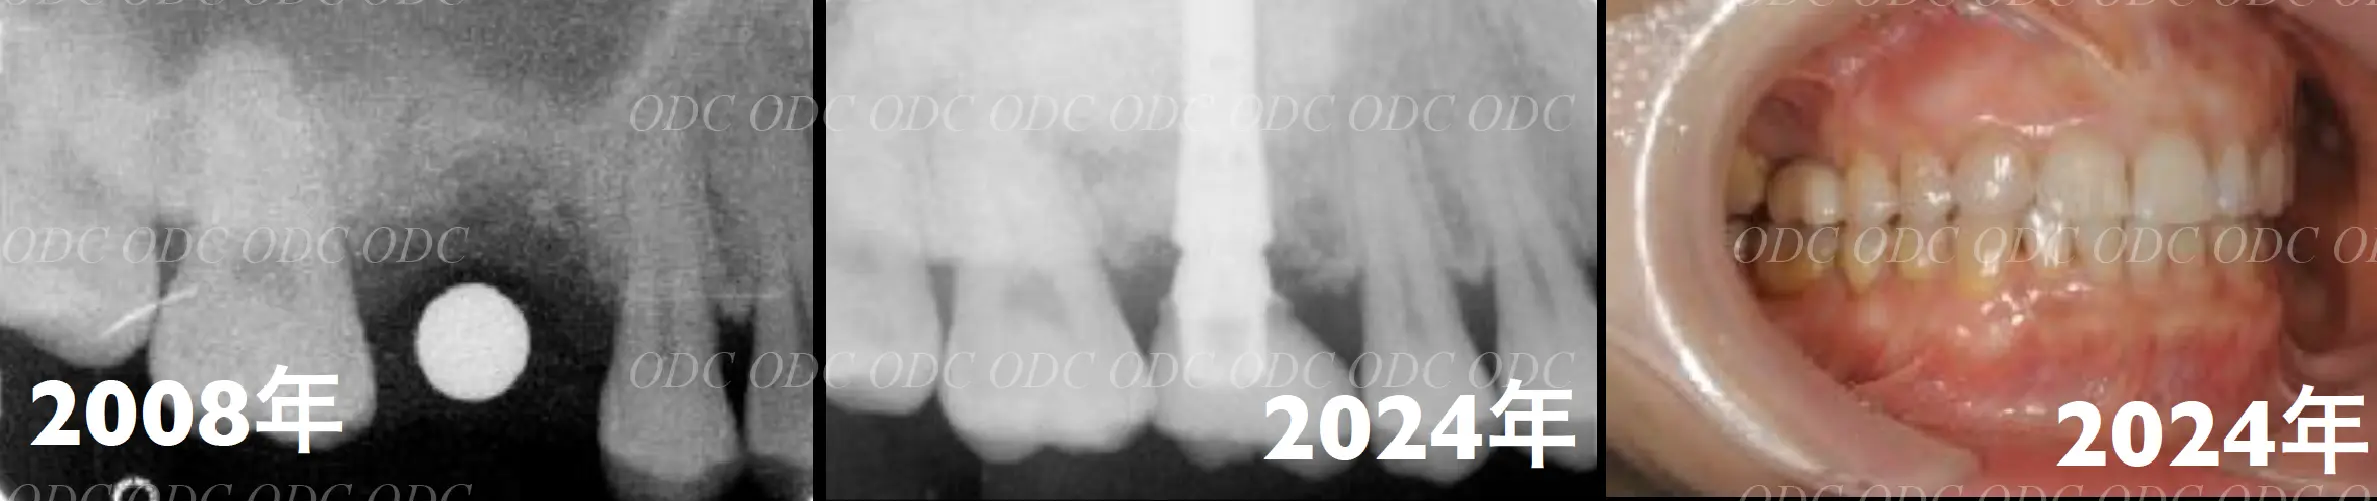

2008年、第一大臼歯の歯根破折を主訴に来院された。

サイナスリフト後にインプラント埋入。

左は術前のレントゲン写真。中央、右は2024年、術後約16年後のレントゲン写真と口腔内写真。